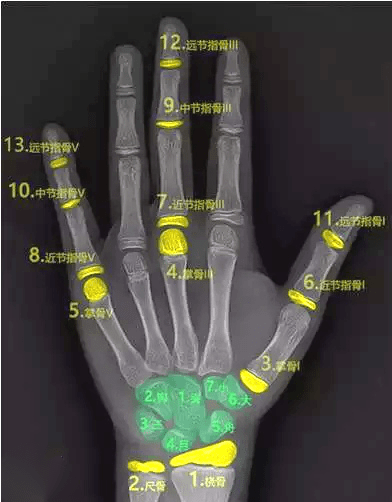

三、骨齡測(cè)試法

骨齡是骨骼年齡的簡(jiǎn)稱,比實(shí)際年齡更能反映人體骨骼的成熟度。

一般是拍攝左手腕部的X線片,觀察指骨、腕骨、橈骨、尺骨下端的骨化中心出現(xiàn)的時(shí)間、面積大小、判斷骨骼實(shí)際發(fā)育程度,來確定骨齡。

如果骨齡小于生活年齡1歲以上,提示有生長激素缺乏癥的可能;骨齡大于生活年齡1歲以上的孩子可能早熟,往往其成年的最終身高反而受損。

因此骨齡異常需要盡早到專業(yè)醫(yī)療機(jī)構(gòu)就診,必要時(shí)進(jìn)行醫(yī)學(xué)干預(yù)和藥物治療。